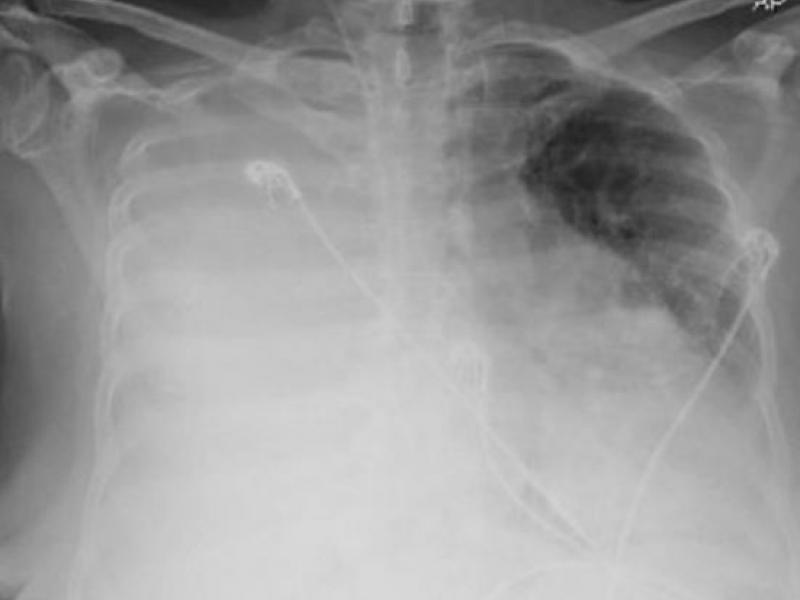

What's the diagnosis?  By Dr. Erica Schramm

January 06 2021

A 48 year old male fell from a ladder landing on his right